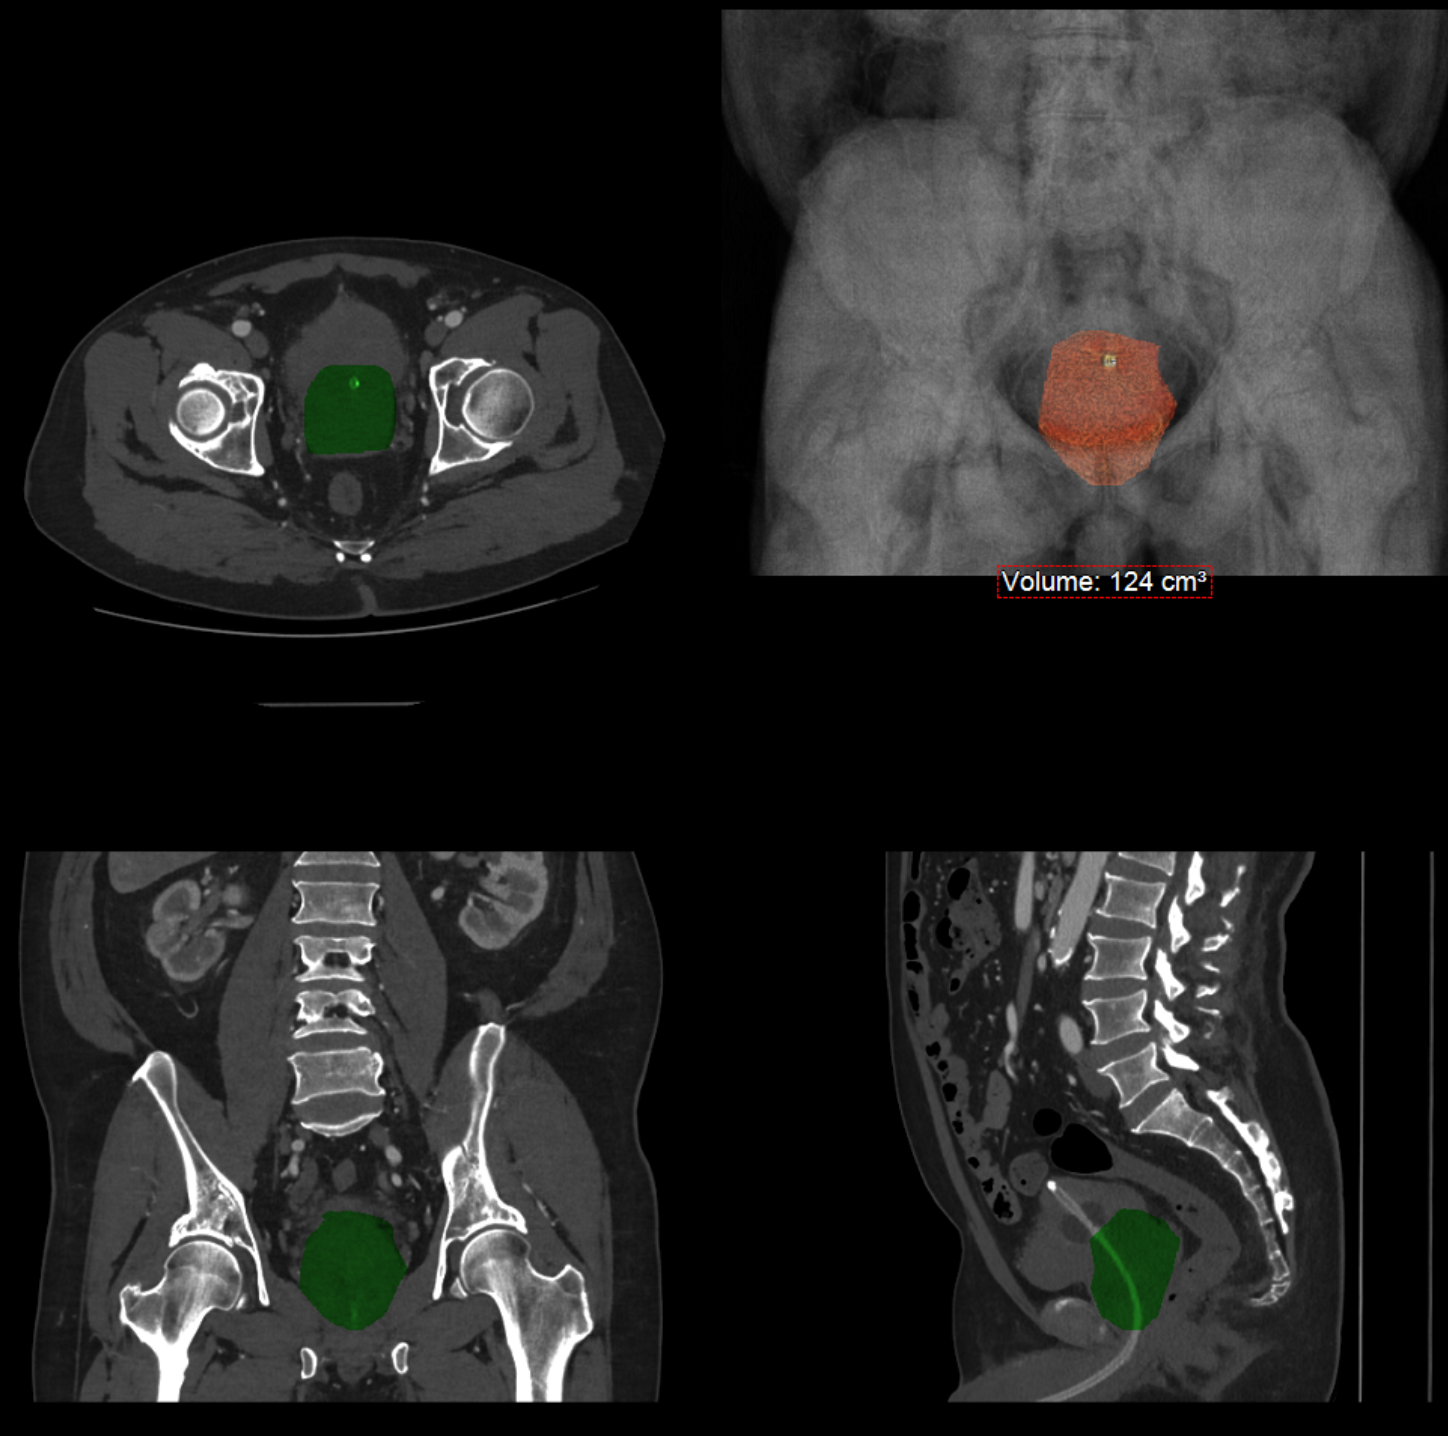

Prostatic Artery Embolisation is performed only when symptomatic Benign Prostatic Hyperplasia is present. The procedure is suitable even for significantly enlarged prostates exceeding 200cc in volume. However, if your prostate volume is less than 40cc, you may not meet the treatment criteria.

Embolisation typically results in gradual prostate volume reduction ranging from 10-50%. Notably, approximately 20% of patients experience symptomatic improvement without measurable changes in prostate size, potentially due to reduced intraglandular pressure (currently under investigation).

The primary objective of embolisation is symptomatic improvement rather than volume reduction, though the latter occurs in most patients as a consequence of atrophy of the abnormal central gland tissue.

If embolisation is considered appropriate, prostate MRI and high-quality CT angiography will be required to evaluate pelvic vasculature and confirm candidacy. Left arm vasculature will also be assessed.